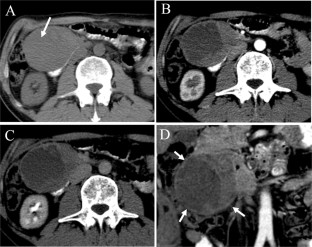

Fig. 1